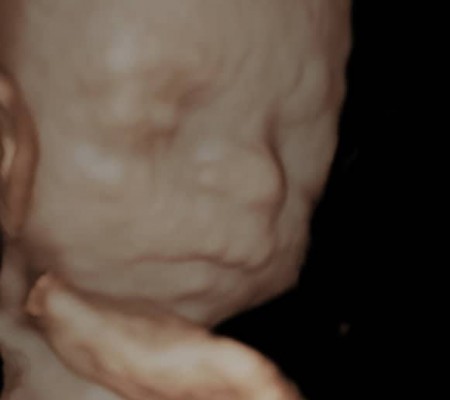

3D i 4D tehnologija omogućava da vidimo površinu bebe na lepši način i pokrete ploda u realnom vremenu.

Takođe nam omogućava da bolje vidimo fetalne mane na licu, šakama i stopalima.

Kao i 2D, 3D i 4D koriste ultrazvučni talas da se kreira slika bebe u materici. 3D je kreirana slika u prostoru dok 4D prikazuje pokret unutar materice pa možemo videti kako se beba smeje, mršti ili zeva.

Da bi se dobile dobre slike poželjno je da se pregled radi između 24 i 32 nedelje trudnoće.